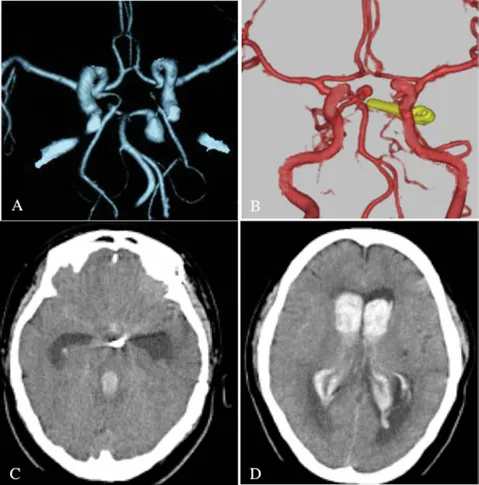

影像学检查提示:头颅CT显示弥漫性蛛网膜下腔出血伴脑室内血肿,此为动脉瘤破裂后最危险并发症,可导致脑组织受压及脑脊液循环障碍;

新发病变确认:3D-CTA(三维计算机断层血管造影)发现基底动脉尖端新发4×4mm动脉瘤,系本次出血责任病灶。

影像资料说明:

(A)七年前3D-CTA显示左侧P1动脉瘤成功夹闭(箭头标示);

(B)本次发病3D-CTA清晰显示基底动脉尖端新发动脉瘤(箭头标示),与既往夹闭位置相邻;

(C&D)CT平扫图像可见广泛蛛网膜下腔出血及脑室内血块,此为导致昏迷的直接原因。